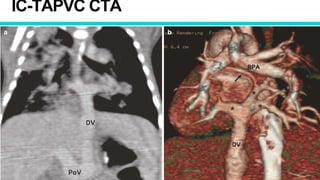

IC-TAPVC CTA

• CTA

✦ Common chamber opening into

CS

✦ Small LA

✦ Dilated RA

✦ ASD